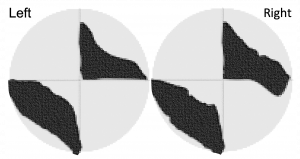

Crossed-quadrant homonymous hemianopsia is also known as the "checkerboard visual field deficit". According to Cross et al., [1], from 1891-1982 there were only 9 reported cases of this deficit documented in the medical literature. As of 2020, there are newer reports associated to Multiple Sclerosis[2][3], Viper bite[4], with different presentations[5]. In this classic deficit, one lesion occurs above the calcarine fissure and one below on the opposite side [6][7]. The defects usually extend across the horizontal median but always respect the vertical median. [8]

Crossed-quadrant homonymous hemianopsia is the homonymous loss of two opposite quadrants of the visual field which is a rare occurrence. Cases of crossed-quadrant homonymous hemianopsia are rare. Visual loss may be sudden or gradual. Visual fields may be affected either simultaneously or in succession, with the former being the most common. It is likely that cerebral infarctions derive principally by embolization of the calcarine arteries from basilar or vertebral branches.

Characteristics of visual field defects: [9][8] [11]

- The defects may arise in

- two simultaneous quandrantanopsias

- two successive homonymous hemianopsia, each resolving into a quadrantanopsia

- simultaneous bilateral homonymous hemianopsia resolving into crossed quadrant defects

- The defects usually extend across the horizontal midline but respect the vertical midline

- There may be sparing of the monocular temporal crescent

- Central vision is usually preserved

- The intact quadrants may demonstrate small areas of field loss

- Color vision may be abnormal

- Riddoch phenomenon may be present which accounts for apparent incongruity of field testing

- Simple or complex visual hallucinations may appear in the blind or seeing field